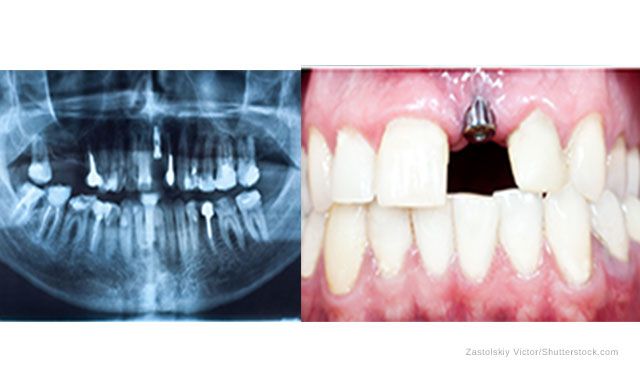

The post and core technique is an excellent option to help preserve natural tooth structure. Because it helps retain as much of the natural tooth as possible, patients avoid bone loss and receding tissue. The post and core technique also helps preserve the integrity of adjacent teeth. Despite the benefits and high occurrence of this procedure, there are several factors that often negatively affect the prognosis of the restoration. Take this short quiz to see if you can you identify some of the most common issues.